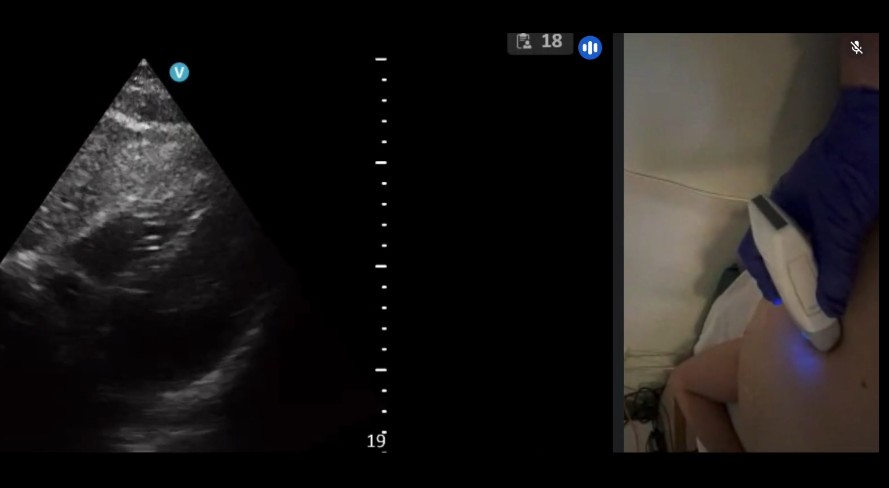

RECURSOS DIDÁCTICOS Inicio » RECURSOS DIDÁCTICOS Videos Documentos Publicaciones Casos clínicos VIDEOS Ver más DOCUMENTOS Checklist muerte encefálica Protocolos de diagnóstico y certificación de la muerte encefálica VSCAN-STROKE: evaluación ultrasonográfica con VSCAN de fuentes embolígenas cardioaórticas por un neurólogo en la fase hiperaguda del ictus isquémico Recomendaciones SONES para realizar estudios ecográficos durante la pandemia SARS-CoV-2 (COVID-19) Impacto de la pandemia covid19 en los laboratorios de neurosonologia Ver más PUBLICACIONES Estado de la neurosonología en España. Un estudio de la Sociedad Española de Neurosonología (SONES). J. Rodríguez-Pardo , J. Carneado-Ruiz, M. Martínez-Martínez, J.M. Moltó-Jordá, P. Irimia, J. Serena-Leal, Ó. Ayo-Martín, P. Martínez Sánchez, J. Pagola J. Fernández-Domínguez Supraesternal aortic debería salir del modo siguiente: Suprasternal aortic arch echocardioscopy as a potential tool in detection and follow-up of mobile thrombi in patients with ischemic stroke. Esnaola Barriola I, Escriche Gorospe E, Miguel Navas P, Martínez Campos E, Molina Goicoechea M, Capell Pascual F, Jiménez Delgado A and Muñoz Arrondo R (2025) Documento de consenso sobre técnicas neurosonológicas en cefaleas. J. Rodríguez Vico, J. Fernández Domínguez, F.J. Julián Villaverde, N. González García, C. García-Cabo Fernández, A. Jaimes Sanchez, O. Ayo Martín, J.A. Membrilla López, R.G. Martínez Martín, J. García Ull, P. Martínez Sánchez, L. Dorado Bouix, R. Belvis Nieto, P. Irimia.Neurología, 2024. Point-of-care ultrasound for transient ischemic attack assessment in transient ischemic attack clinics: Consensus document of the Spanish Society of Neurosonology. Amaya-Pascasio, L., Rodríguez-Pardo de Donlebún, J., Arjona-Padillo, A., Fernández-Domínguez, J., Martínez-Martínez, M., Muñoz-Arrondo, R., García-Sánchez, J. M., Pagola Pérez de la Blanca, J., Carneado-Ruiz, J., & Martínez-Sánchez, P. Neurología. 2024 Increased vertebral canal diameter measured by ultrasonography as a sign of vasculitis in patients with giant cell arteritis. Ayo-Martín O, Segura T et al. Frontiers in Medicine 2023 Transcranial sonography in atypical parkinsonism: how reliable is it in real clinical practice? A multicentre comprehensive study. Alonso Cánovas A, Tembl Ferrairó JI, Martínez-Torres I, López-Sendón Moreno JL, Paree-Moreno I, Monreal-Laguillo E et al. Parkinsonism related disorders 2019; 68: 40-45 Qué debería saber el médico de familia sobre la ecografía transcraneal en neurología. Fernández Domínguez J. FMC 2016; 23 (8): 467-473 Evaluación de la sustancia negra mediante ultrasonografía transcraneal. Vivó-Orti M, Tembl JI, Sastre-Bataller I, Vázquez-Costa JF, Sahuquillo P, Burguera JA. Rev Neurol 2013; 56 (5): 268-274 Utilidad del duplex orbitario para la valoración de atrofia del nervio óptico en enfermedades desmielinizantes: estudio piloto. Fernández-Domínguez J, García-Rodríguez R, Mateos V. Rev Neurol 2012; 54 (10): 587-592 Dúplex transcraneal en la enfermedad de moyamoya. Vázquez-Sánchez F, López-Veloso M, Argandoña-Palacios L, Segura T. Rev Neurol 2012; 54 (2): 249-250 Ver más CASOS CLÍNICOS Caso 7 – 2023 Ver caso Ver todos los casos SONES SOCIEDAD ESPAÑOLADE NEUROSONOLOGÍA secretariasones@gmail.com HAZTE SOCIO ¡Síguenos en Twitter!